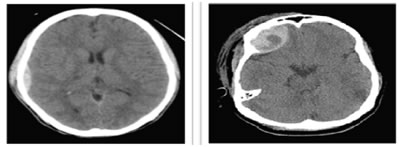

- On CT it appears as hyperdense(60-90HU), biconvex shaped collection in the extra-axial region ,Presence of hypodense area inside hyperdense lesion indicates active bleeding (“Swirl Sign”)11 Fig 7. Itcan cross falx and tentorium but does not cross suture lines.

Figure 6: Figure 7:

Figure 6: A 15-year old boy who presented after a road traffic accident, Axial NECT scan reveals, acute EDH was along the right parietal convexity.

Figure 7: A 17 year old presented after fall from bike, Axial NECT scan reveals, lens like or biconvex shaped EDH in right frontal location, heterogeneous appearance indicated active bleeding -swirl sign.